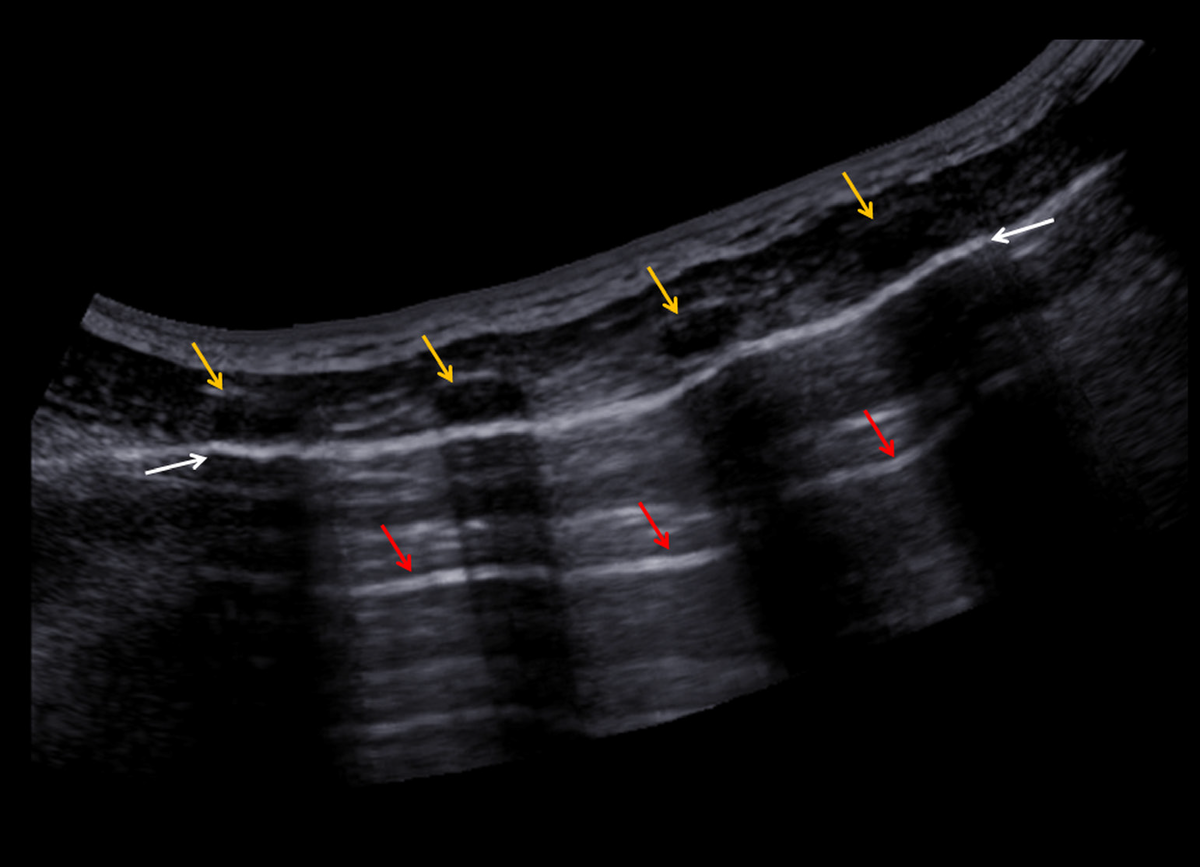

Ультразвуковое исследование выполнено портативным аппаратом Samsung HM70A с конвексным CA1-7AD и линейным LA3-16AD датчиками, непосредственно в отделении неотложной помощи. Представленные ниже результаты УЗИ хорошо коррелируют с результатами рентгенографии грудной клетки (рис. 2, A-D).

• С помощью линейного датчика, морфологические изменения в субплевральных участках легких не были обнаружены.

• При использовании конвексного датчика изменения содержания воздуха и жидкости в легких, косвенного признака консолидации легочных тканей, и симптом «воздушной бронхограммы» не обнаружены.

• Диагностика заболевания легких основана на артефактах поражения легочной ткани. Наличие A-линий и отсутствие B-линий является косвенным признаком здорового легкого без какой-либо периферической консолидации или отека легких.

• Динамическое обследование межреберных мышц продемонстрировало нормальную картину во время вдоха и выдоха. Не обнаружено утолщения и неровности плевральной линии в процессе визуализации нормального скольжения листков плевры.

Рис. 2A. На панорамном ультразвуковом изображении видна стенка грудной клетки и плевра (ребра: желтые стрелки, плевра: белые стрелки). А-линии это яркие горизонтальные линии глубже плевральной линии (красные стрелки). A-линии - классический артефакт реверберации.